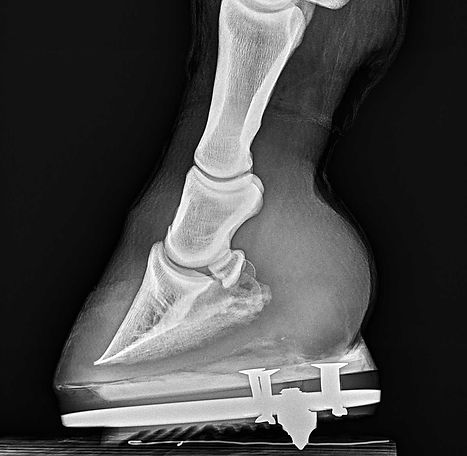

X-Ray (Ultra HD)